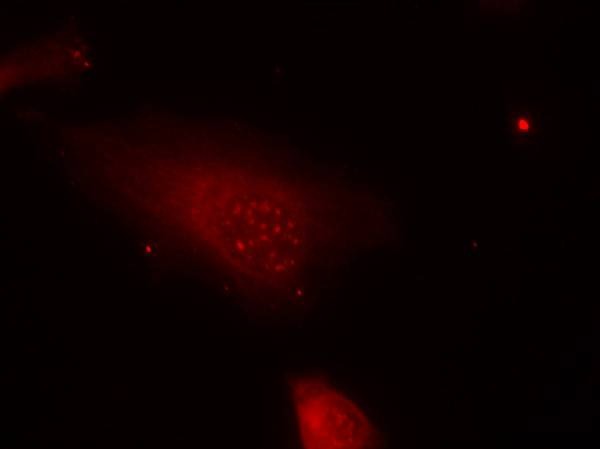

| Verified Activity | 1. Western blot analysis of extracts from 3T3 cells untreated or treated with serum starvation using FKHR (Phospho-Ser319) Antibody TMAC-01494. 2. Immunohistochemical analysis of paraffin-embedded human breast carcinoma tissue using FKHR (Phospho-Ser319) Antibody TMAC-01494 (left) or the same antibody preincubated with blocking peptide (right). 3. Immunofluorescence staining of methanol-fixed Hela cells using FKHR (Phospho-Ser319) Antibody TMAC-01494. ![]() ![]() ![]() |